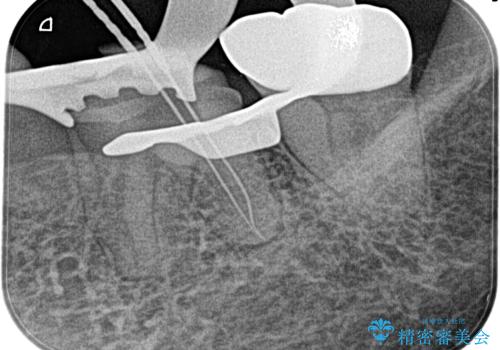

奥歯がズキズキ痛い 根管治療

- 冷たいもので強い痛みがあり、1週間前ぐらいからズキズキ痛いことを主訴に来院されました。

患歯に冷温刺激に対し20秒の持続痛と打診を認めたため、不可逆性歯髄炎の診断とし治療を行なっております。

- 精密根管治療(イニシャルケース,大臼歯):122,000円、ファイバーコア:22,000円費用は治療当時の料金となります

不可逆性歯髄炎と診断される場合は、経過観察を行なっても正常歯髄に戻る可能性は極めて低いため今回の処置のように抜髄の適応となります。